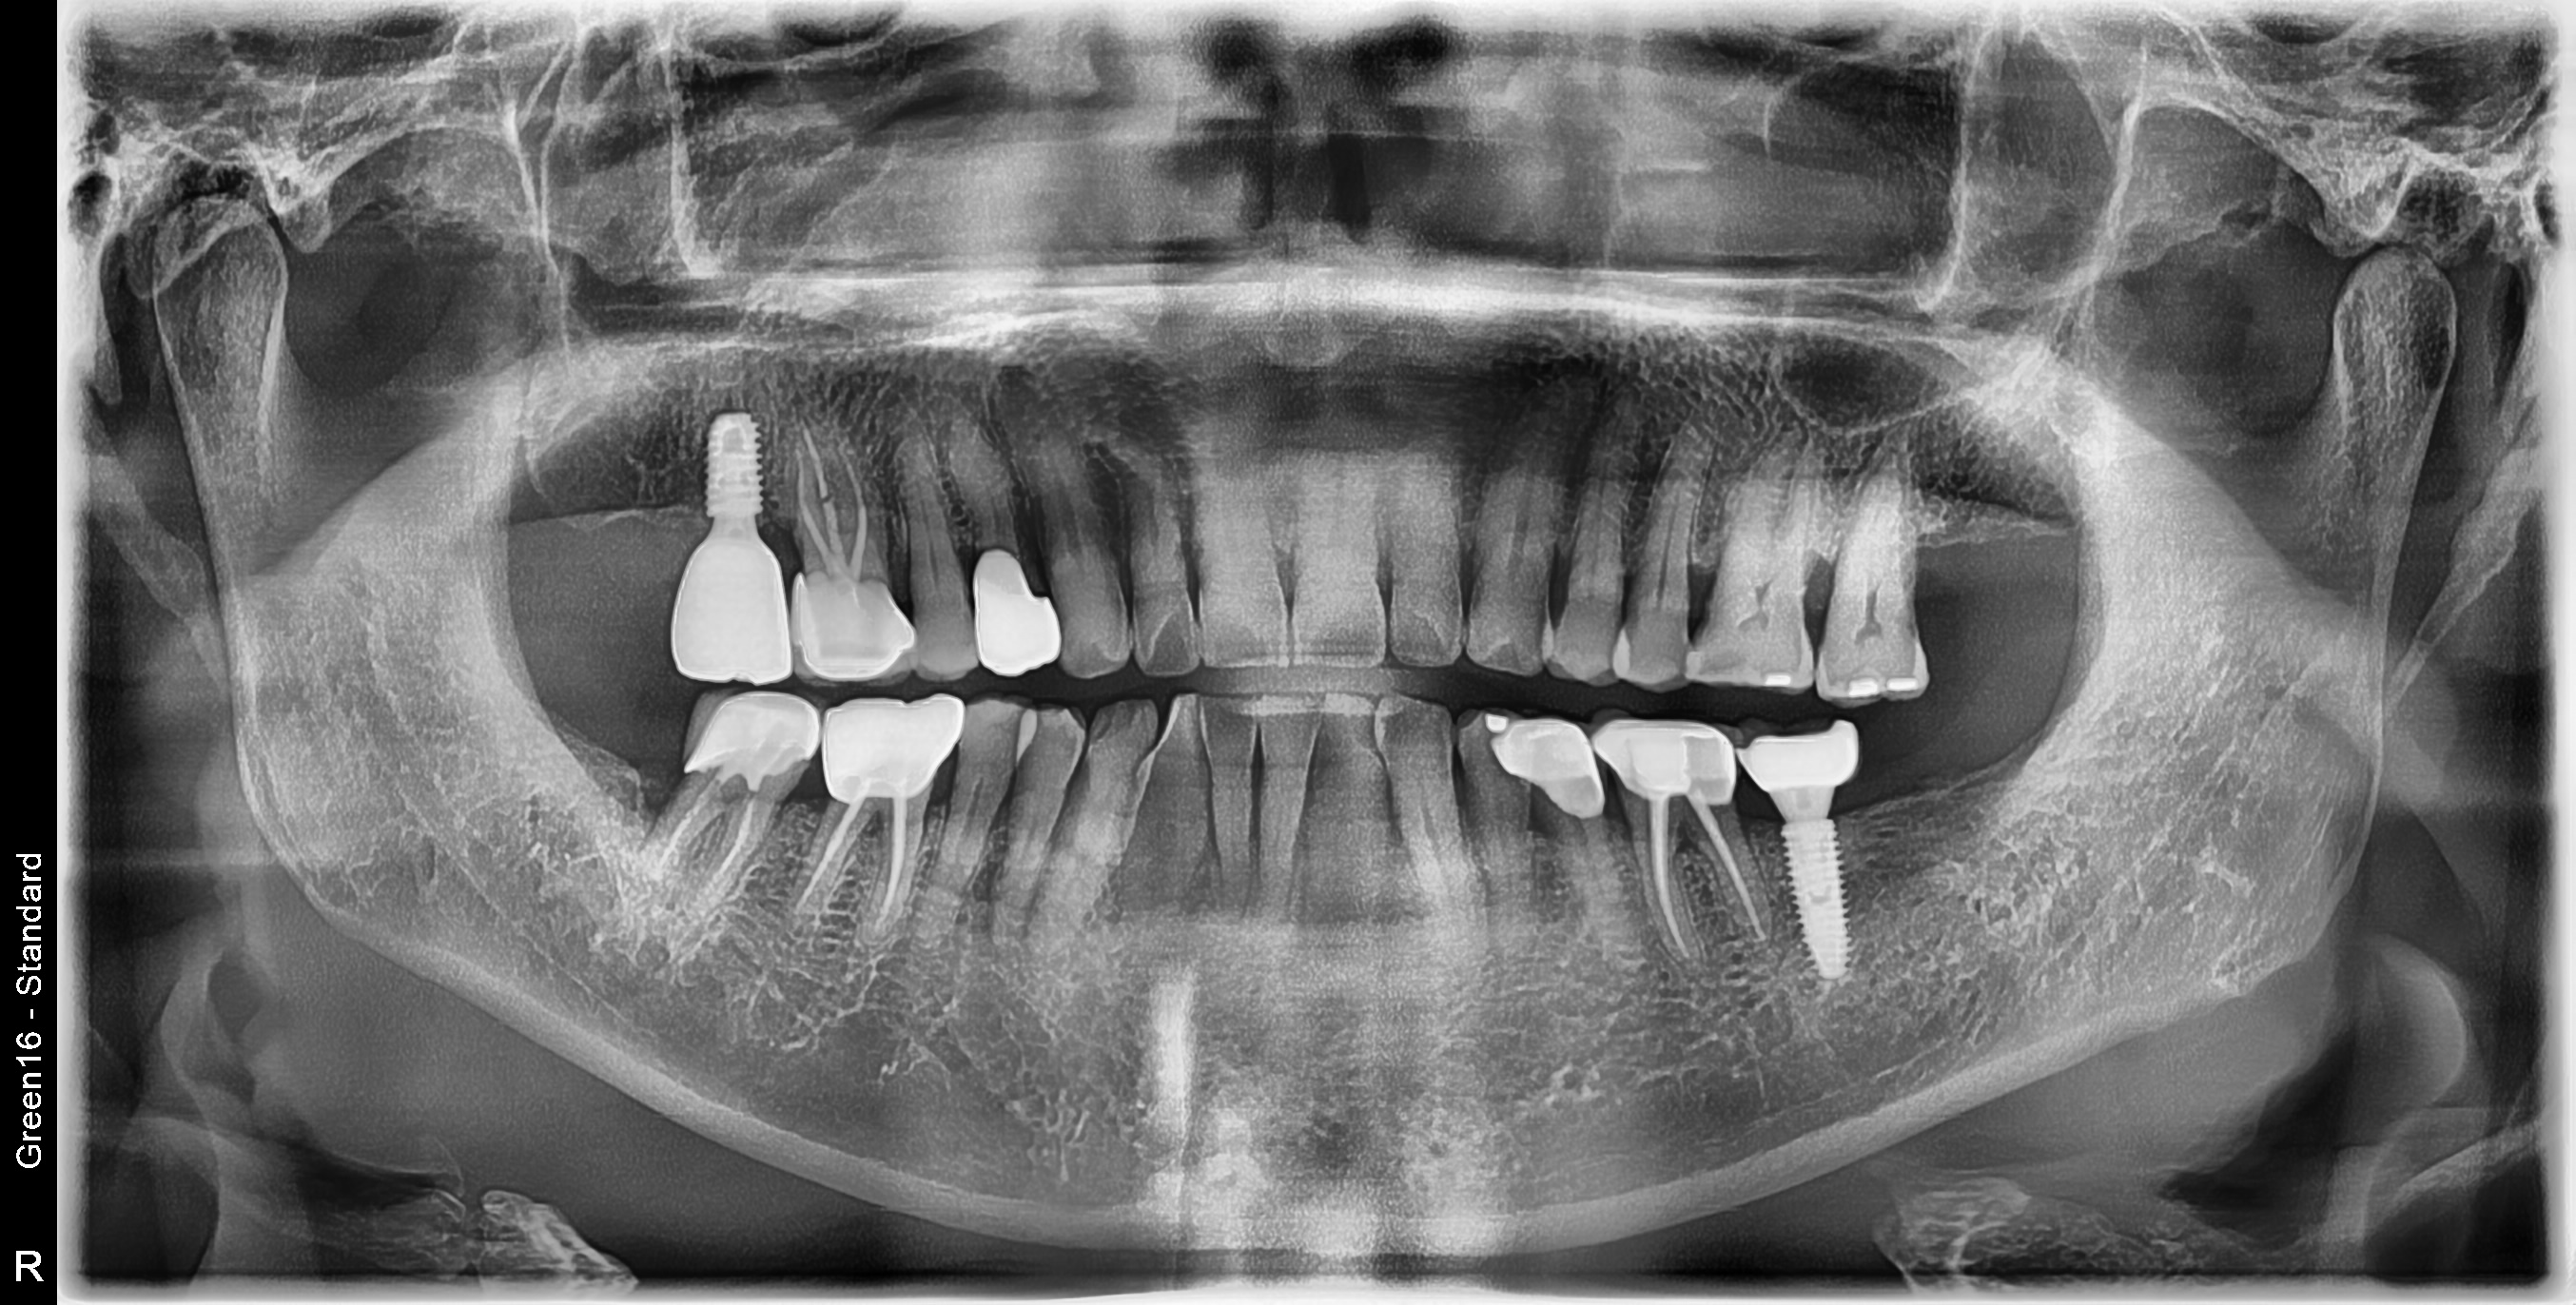

발치 즉시 임플란트 식립사례

전후사진

수술 전

수술 후

구치부 임플란트 식립사례